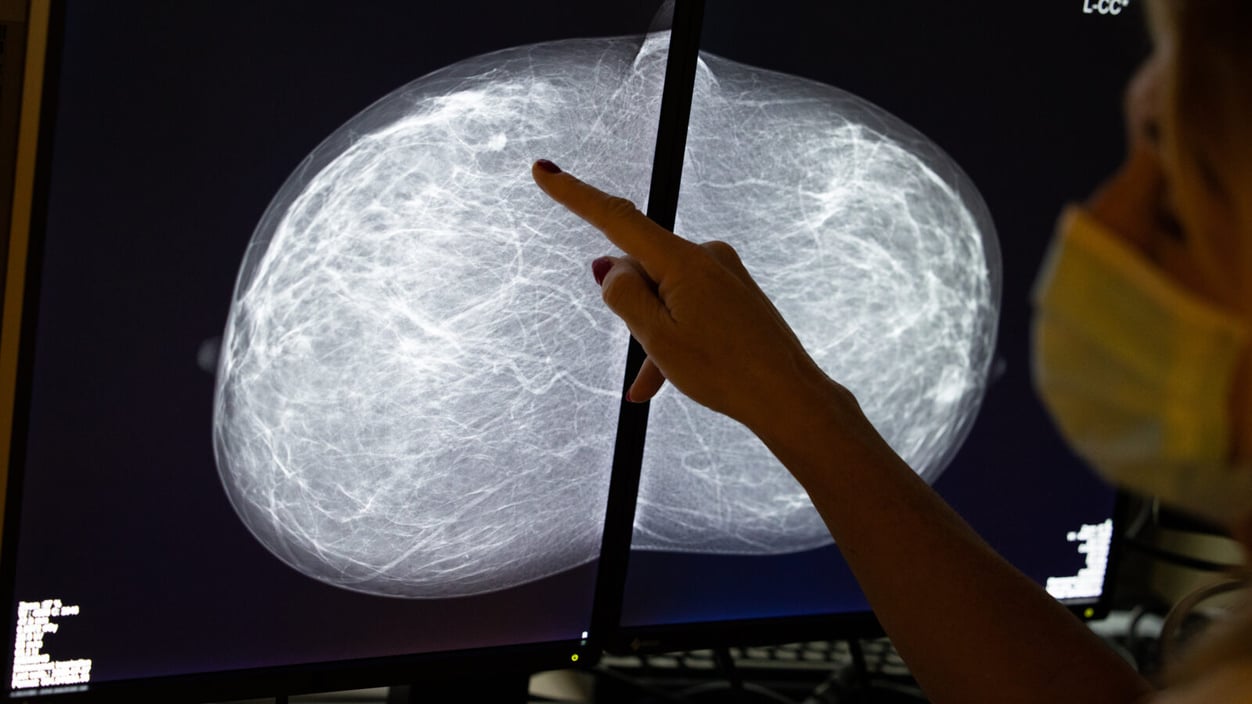

We know dense breast tissue raises cancer risk. What's next?

Benoit Doppagne/Belga Mag/AFP via Getty Images

Having dense breasts can be problematic in two ways when getting a mammogram to detect cancer. There's a higher risk of cancer in fibrous tissue, and it's harder to see potential tumors because dense tissue looks like cancer in the image. That's why 38 U.S. states require health care providers to tell patients if they have dense breasts. But what happens next isn't so clear. Even though dense breasts are normal, there is no consensus on how best to screen for cancer if mammography falls short.

Breast ultrasounds are one option, but high rates of false positives makes it less than ideal. MRIs are typically reserved for patients who have increased risk. Research is ongoing into such options as abbreviated MRIs, but as always, paying for these tests and finding a way to a center that offers them pose other barriers. STAT's Annalisa Merelli explores this issue.